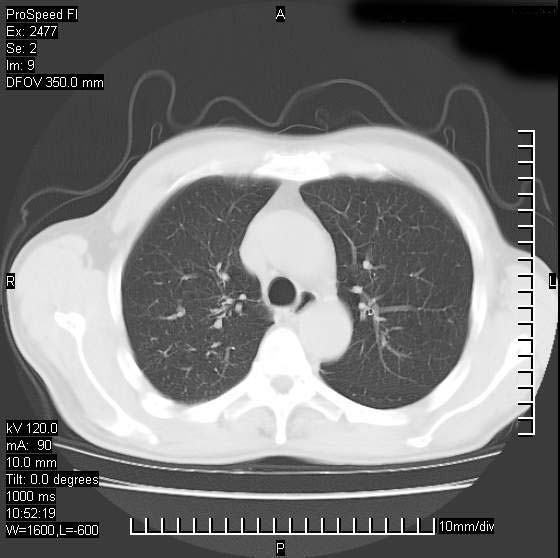

以下是引用天南地北在2007-10-9 14:29:00的发言:[br]1:右上肺结核[br]2:右肺下叶肿块:不支持肺癌,首先考虑炎性病变-肺脓疡可能性大[br]理由:1:临床病史支持,肺脓肿症状不明显应该是不规则服药造成。[br] 2:肿块边缘模糊,周围可见炎性渗出,长毛刺,内见支气管征,不过有点不规则。[br] 我感觉下肺癌这个诊断有点偏左,建议积极抗炎治疗后复查

以下是引用卜一在2007-10-9 15:55:00的发言:[br][br] [br] 1:右上肺结核[br]2:右肺下叶肿块:不支持肺癌,首先考虑炎性病变-肺脓疡可能性大[br]理由:1:临床病史支持,肺脓肿症状不明显应该是不规则服药造成。[br] 2:肿块边缘模糊,周围可见炎性渗出,长毛刺,内见空气支气管征,不过有点不规则。[br] 我感觉下肺癌这个诊断有点偏左,建议积极抗炎治疗后复查![br]支持! [br] [br] [br]

以下是引用wxy7406在2007-10-9 21:02:00的发言:[br]结合临床病史首先考虑感染性病变,但周围型肺癌不能除外,1.患者年龄偏大2.临床有咯血3.(也觉得是最重要的一点)病灶内有偏心性空洞。

以下是引用王仕学在2007-10-9 13:48:00的发言:[br]右下肺周围性肺癌可能性大,最好活检吧

以下是引用hhcckk在2007-10-9 15:18:00的发言:[br]右上肺病灶考虑结核,病灶多种形态并存(纤维化、增殖性病灶并存)[br]右下肺病灶比较难说,个人意见更趋向于“天南地北”的诊断----肺脓肿[br]1、病人有明显的寒战,高热,肿瘤病人很少出现[br]2、病灶周围的肺纹理走向柔和,没有肿瘤病灶常见的集束征[br]3、病灶边缘的毛刺较长,恶性肿瘤多为短毛刺[br]痰中血丝和病人的年龄是两个不利于良性肿块的因素,建议早点活检

以下是引用ydx_74在2007-10-9 15:53:00的发言:[br]右上肺结核,右下中心性肺癌可能大,肺门淋巴结肿大。